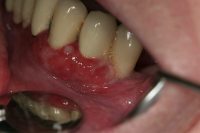

Ödematös, rodnad och blödande gingiva.

Karakteriseras av approximala nekrotiska och fibrintäckta sår (nedsmälta papiller) som är smärtsamma vid beröring och mycket lättblödande.

Patienten kan ha påverkat allmän tillstånd och ofta foeter ex ore.